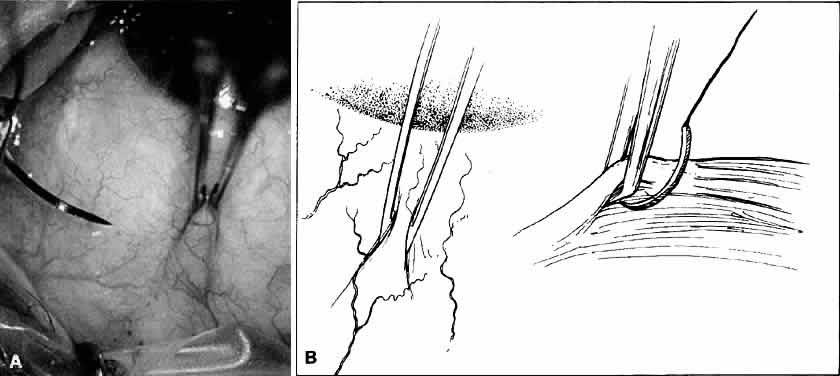

The first step in ocular microsurgery is maintaining separation of the eyelids. This separation involves not only opening the lids beyond their natural opening but also retracting the lids from the globe to relieve the natural deformation of the globe, which may be caused by the eyelids. In addition, should the patient inadvertently attempt to blink during surgery, this action will not result in increased intraocular pressure (IOP). Lid separation may be maintained by traction sutures or lid specula. Traction sutures are effective in obtaining lid separation and retraction (Fig. 9). Traction sutures are most effective when passed through the tarsus; however, there is a tendency for the lids to evert. The tarsus lid speculum may be either self-retaining or of the spring-tension type (Fig. 10). In addition, individual lid hooks or retractors that are maintained by clamping to the head drape may be used. Each speculum offers certain advantages. Some specula, which offer the additional option of aspiration, may be attached to suction devices to keep the fornices dry during the procedure. The spring-tension wire or solid-blade speculum opens the lids to the extent of the spring tension. However, spring tension is not adjustable, and the speculum may rotate intraoperatively. Many lid speculum designs are available with a screw clamp design. A lid speculum with a screw clamp device, such as the Schott lid speculum, allows the lids to be separated and retracted off the globe when the lid hooks are everted individually.5 This lid speculum provides an excellent surgical field without resulting in increased IOP. This feature is especially important if the assistant inadvertently leans on the lid speculum during the operation. In another type, the Jaffe lid speculum, the upper and lower lid hooks are individually secured to the head drape. This type of speculum offers some advantage when operating on patients with a prominent brow or deep-set orbits. The wire speculum may be formed to the patient's brow to allow for better retraction of the upper lid. With any of these methods, it is theoretically possible to disinsert the levator muscle from the superior aspect of the tarsus, resulting in postoperative ptosis. Therefore, overretraction of the lids must be avoided.

Fig. 9. A traction suture is placed through the skin and tarsus to provide traction on the lid. However, there is a tendency for the lids to evert during the procedure.